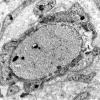

6D1C Onion-Bulb (Case 6)_057 - Copy